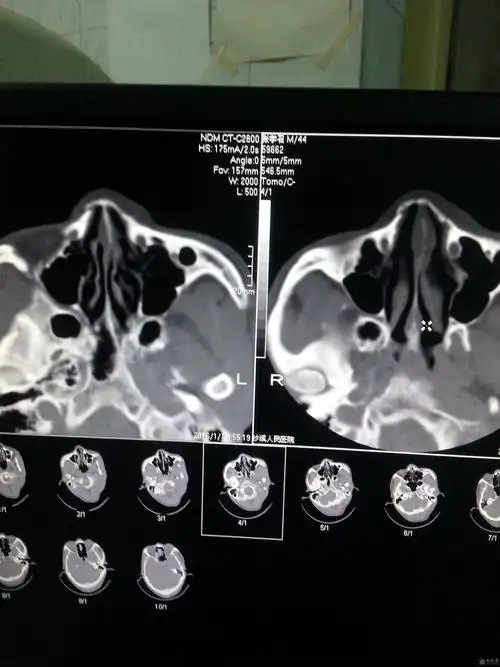

鼻骨骨折了吗